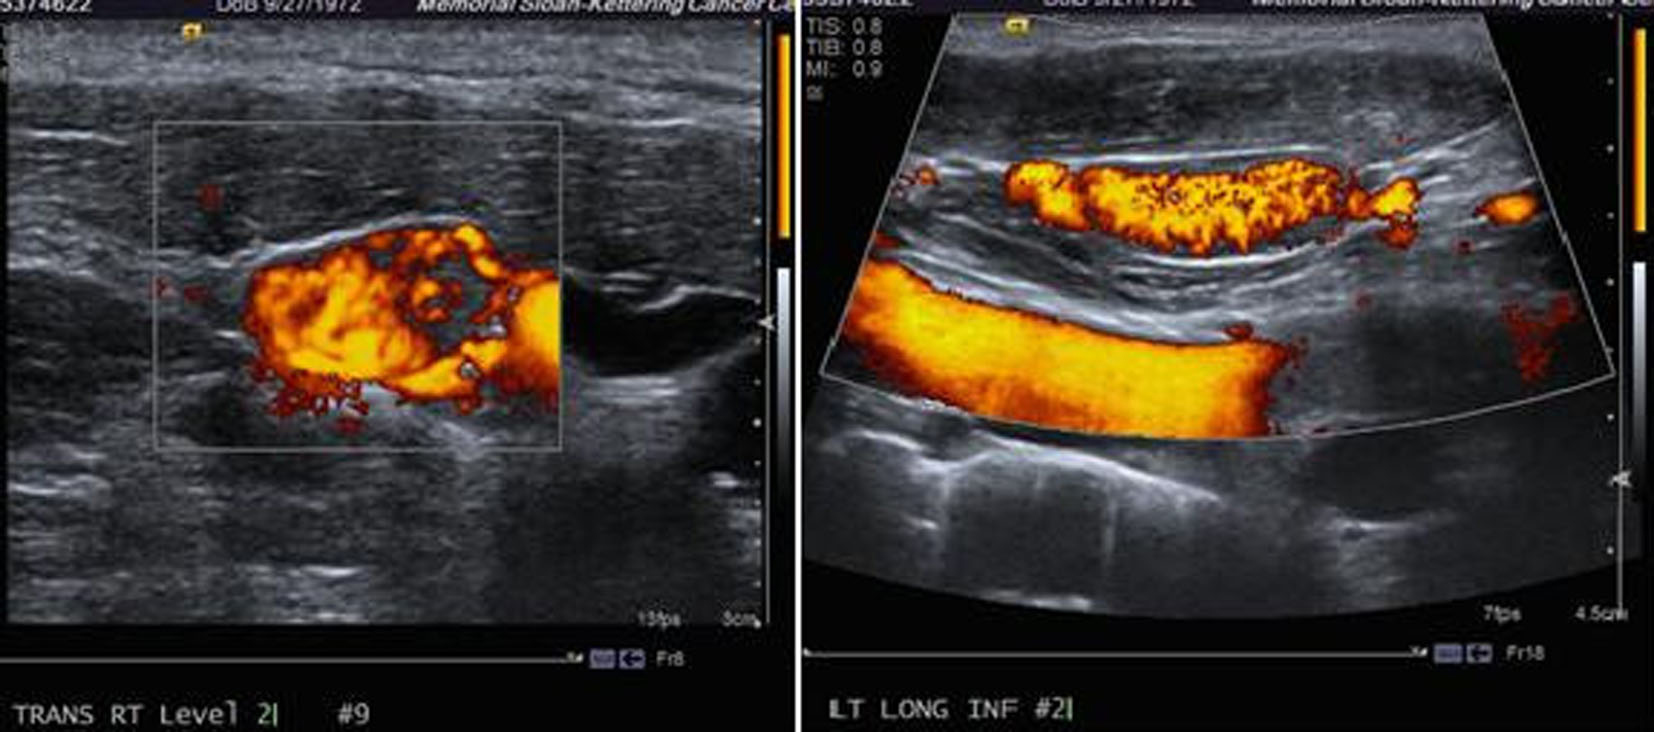

Ultrasound of the neck revealed: right lobe measuring 5.2 × 1.8 × 2.1 cm with a hypoechoic nodule and calcifications in the mid lobe, left lobe measuring 4.5 × 2 × 2.6 cm with a few cystic nodules and extensive bilateral cervical adenopathy (Fig. 1).

![]() Click for large image | Figure 1. Ultrasound of the neck showing a thyroid mass suspicious of malignancy. |